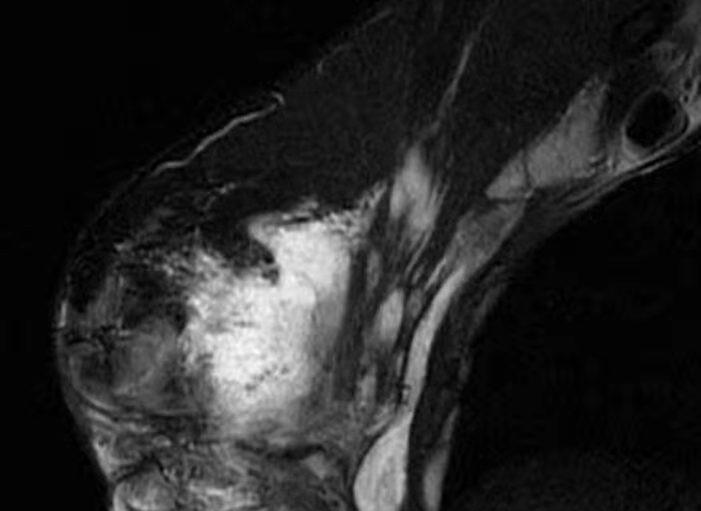

果不其然 , 在检查完后 , CT显示她的乳房内有大量的乳白色的液体 , 即注射进去的奥美定 。 为了减轻胸部的焦灼感 , 红粉宝宝只好赶紧把它取出来 。 尽管如此 , 她的胸部到后来仍几乎丧失了全部知觉 。